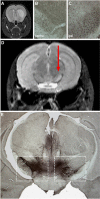

As a sequel of brain ischemia, selective neuronal loss (SNL)-as opposed to pannecrosis (i.e. infarction)-is attracting growing interest, particularly because it is now detectable in vivo. In acute stroke, SNL may affect the salvaged penumbra and hamper functional recovery following reperfusion. Rodent occlusion models can generate SNL predominantly in the striatum or cortex, showing that it can affect behavior for weeks despite normal magnetic resonance imaging. In humans, SNL in the salvaged penumbra has been documented in vivo mainly using positron emission tomography and (11)C-flumazenil, a neuronal tracer validated against immunohistochemistry in rodent stroke models. Cortical SNL has also been documented using this approach in chronic carotid disease in association with misery perfusion and behavioral deficits, suggesting that it can result from chronic or unstable hemodynamic compromise. Given these consequences, SNL may constitute a novel therapeutic target. Selective neuronal loss may also develop at sites remote from infarcts, representing secondary 'exofocal' phenomena akin to degeneration, potentially related to poststroke behavioral or mood impairments again amenable to therapy. Further work should aim to better characterize the time course, behavioral consequences-including the impact on neurological recovery and contribution to vascular cognitive impairment-association with possible causal processes such as microglial activation, and preventability of SNL.